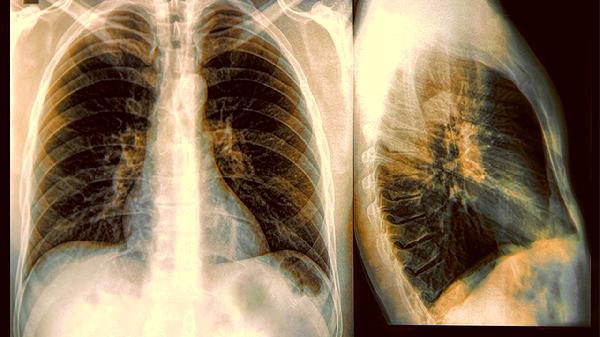

2.检查方式有门道

普通胸片可能会漏掉小饼干屑般的结节,低剂量CT才是靠谱选择。这就像用筛子捞鱼和用渔网捕鱼的差别,工具选对了才能兜住重要信息。